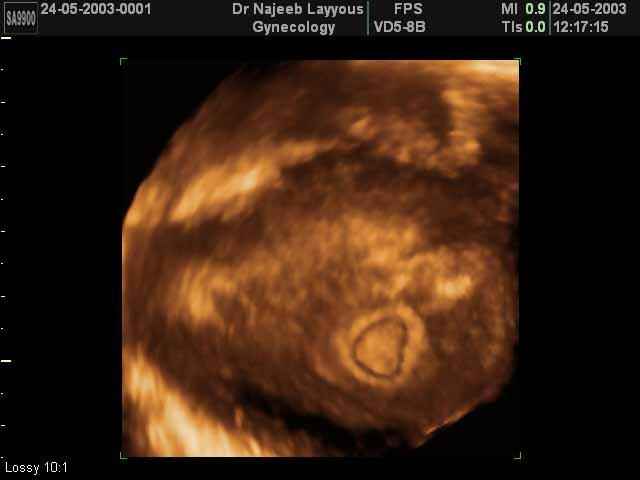

- 3D Photos Ecographie du Premier Trimestre

3D Photos Ecographie du Premier Trimestre (Photos d’échographie de tôt grossesse)| Dr N Layyous